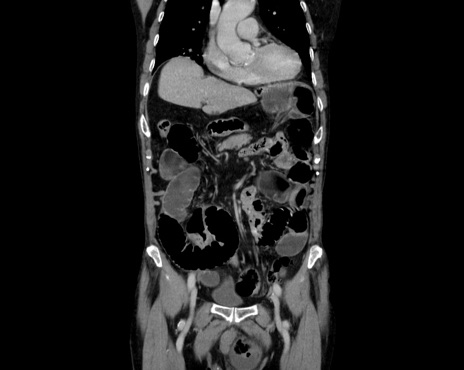

症例26(冠状断像)

【症例】80歳代男性

【主訴】嘔吐

【現病歴】昨晩2回嘔吐あり、今朝になっても嘔吐あり。来院。

【既往歴】胃潰瘍

【身体所見】意識清明、BT 37.6℃、BP 166/95mmHg、HR 100bpm、SpO2 97%、腹部:平坦・軟、腸蠕動音聴取良好、圧痛なし。

【データ】WBC 21900、CRP 1.4

横断像